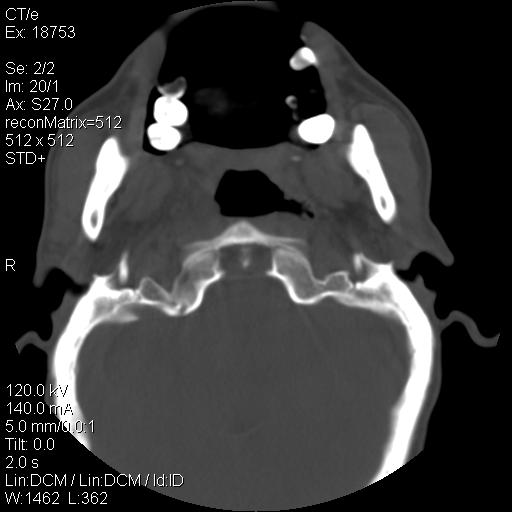

标题: CT21693:男 58岁 右侧咽部疼她2天余 PE:右侧扁桃体肿大 压痛 [打印本页]

标题: CT21693:男 58岁 右侧咽部疼她2天余 PE:右侧扁桃体肿大 压痛

右化脓性扁桃体炎症伴咽后壁脓肿形成.